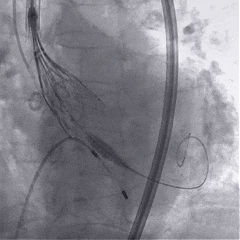

术中影像

根部造影

球囊预扩

瓣膜稳定释放

瓣膜展开后造影

再次造影,确认瓣膜位置

稳定脱钩

最终造影,瓣膜位置良好,无明显瓣周漏

外周血管检查